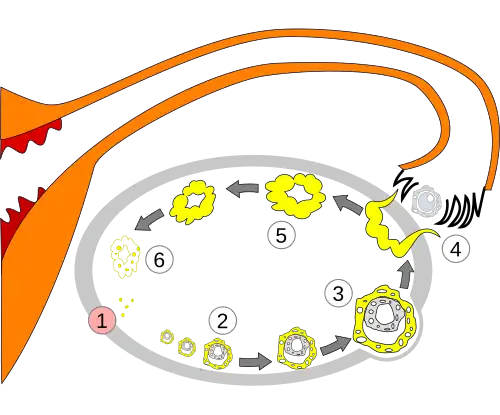

Development and structure

The corpus luteum develops from an ovarian follicle during the luteal phase of the menstrual cycle or oestrous cycle, following the release of a secondary oocyte from the follicle during ovulation. The follicle first forms a corpus hemorrhagicum before it becomes a corpus luteum, but the term refers to the visible collection of blood, left after rupture of the follicle, that secretes progesterone. While the oocyte (later the zygote if fertilization occurs) traverses the fallopian tube into the uterus, the corpus luteum remains in the ovary.

Its cells develop from the follicular cells surrounding the ovarian follicle.[5] The follicular theca cells luteinize into small luteal cells (thecal-lutein cells) and follicular granulosa cells luteinize into large luteal cells (granulosal-lutein cells) forming the corpus luteum. Progesterone is synthesized from cholesterol by both the large and small luteal cells upon luteal maturation. Cholesterol-LDL complexes bind to receptors on the plasma membrane of luteal cells and are internalized. Cholesterol is released and stored within the cell as cholesterol ester. LDL is recycled for further cholesterol transport. Large luteal cells produce more progesterone due to uninhibited/basal levels of protein kinase A (PKA) activity within the cell. Small luteal cells have LH receptors that regulate PKA activity within the cell. PKA actively phosphorylates steroidogenic acute regulatory protein (StAR) and translocator protein to transport cholesterol from the outer mitochondrial membrane to the inner mitochondrial membrane.[6]

The development of the corpus luteum is accompanied by an increase in the level of the steroidogenic enzyme P450scc that converts cholesterol to pregnenolone in the mitochondria.[7] Pregnenolone is then converted to progesterone that is secreted out of the cell and into the blood stream. During the bovine estrous cycle, plasma levels of progesterone increase in parallel to the levels of P450scc and its electron donor adrenodoxin, indicating that progesterone secretion is a result of enhanced expression of P450scc in the corpus luteum.[7]